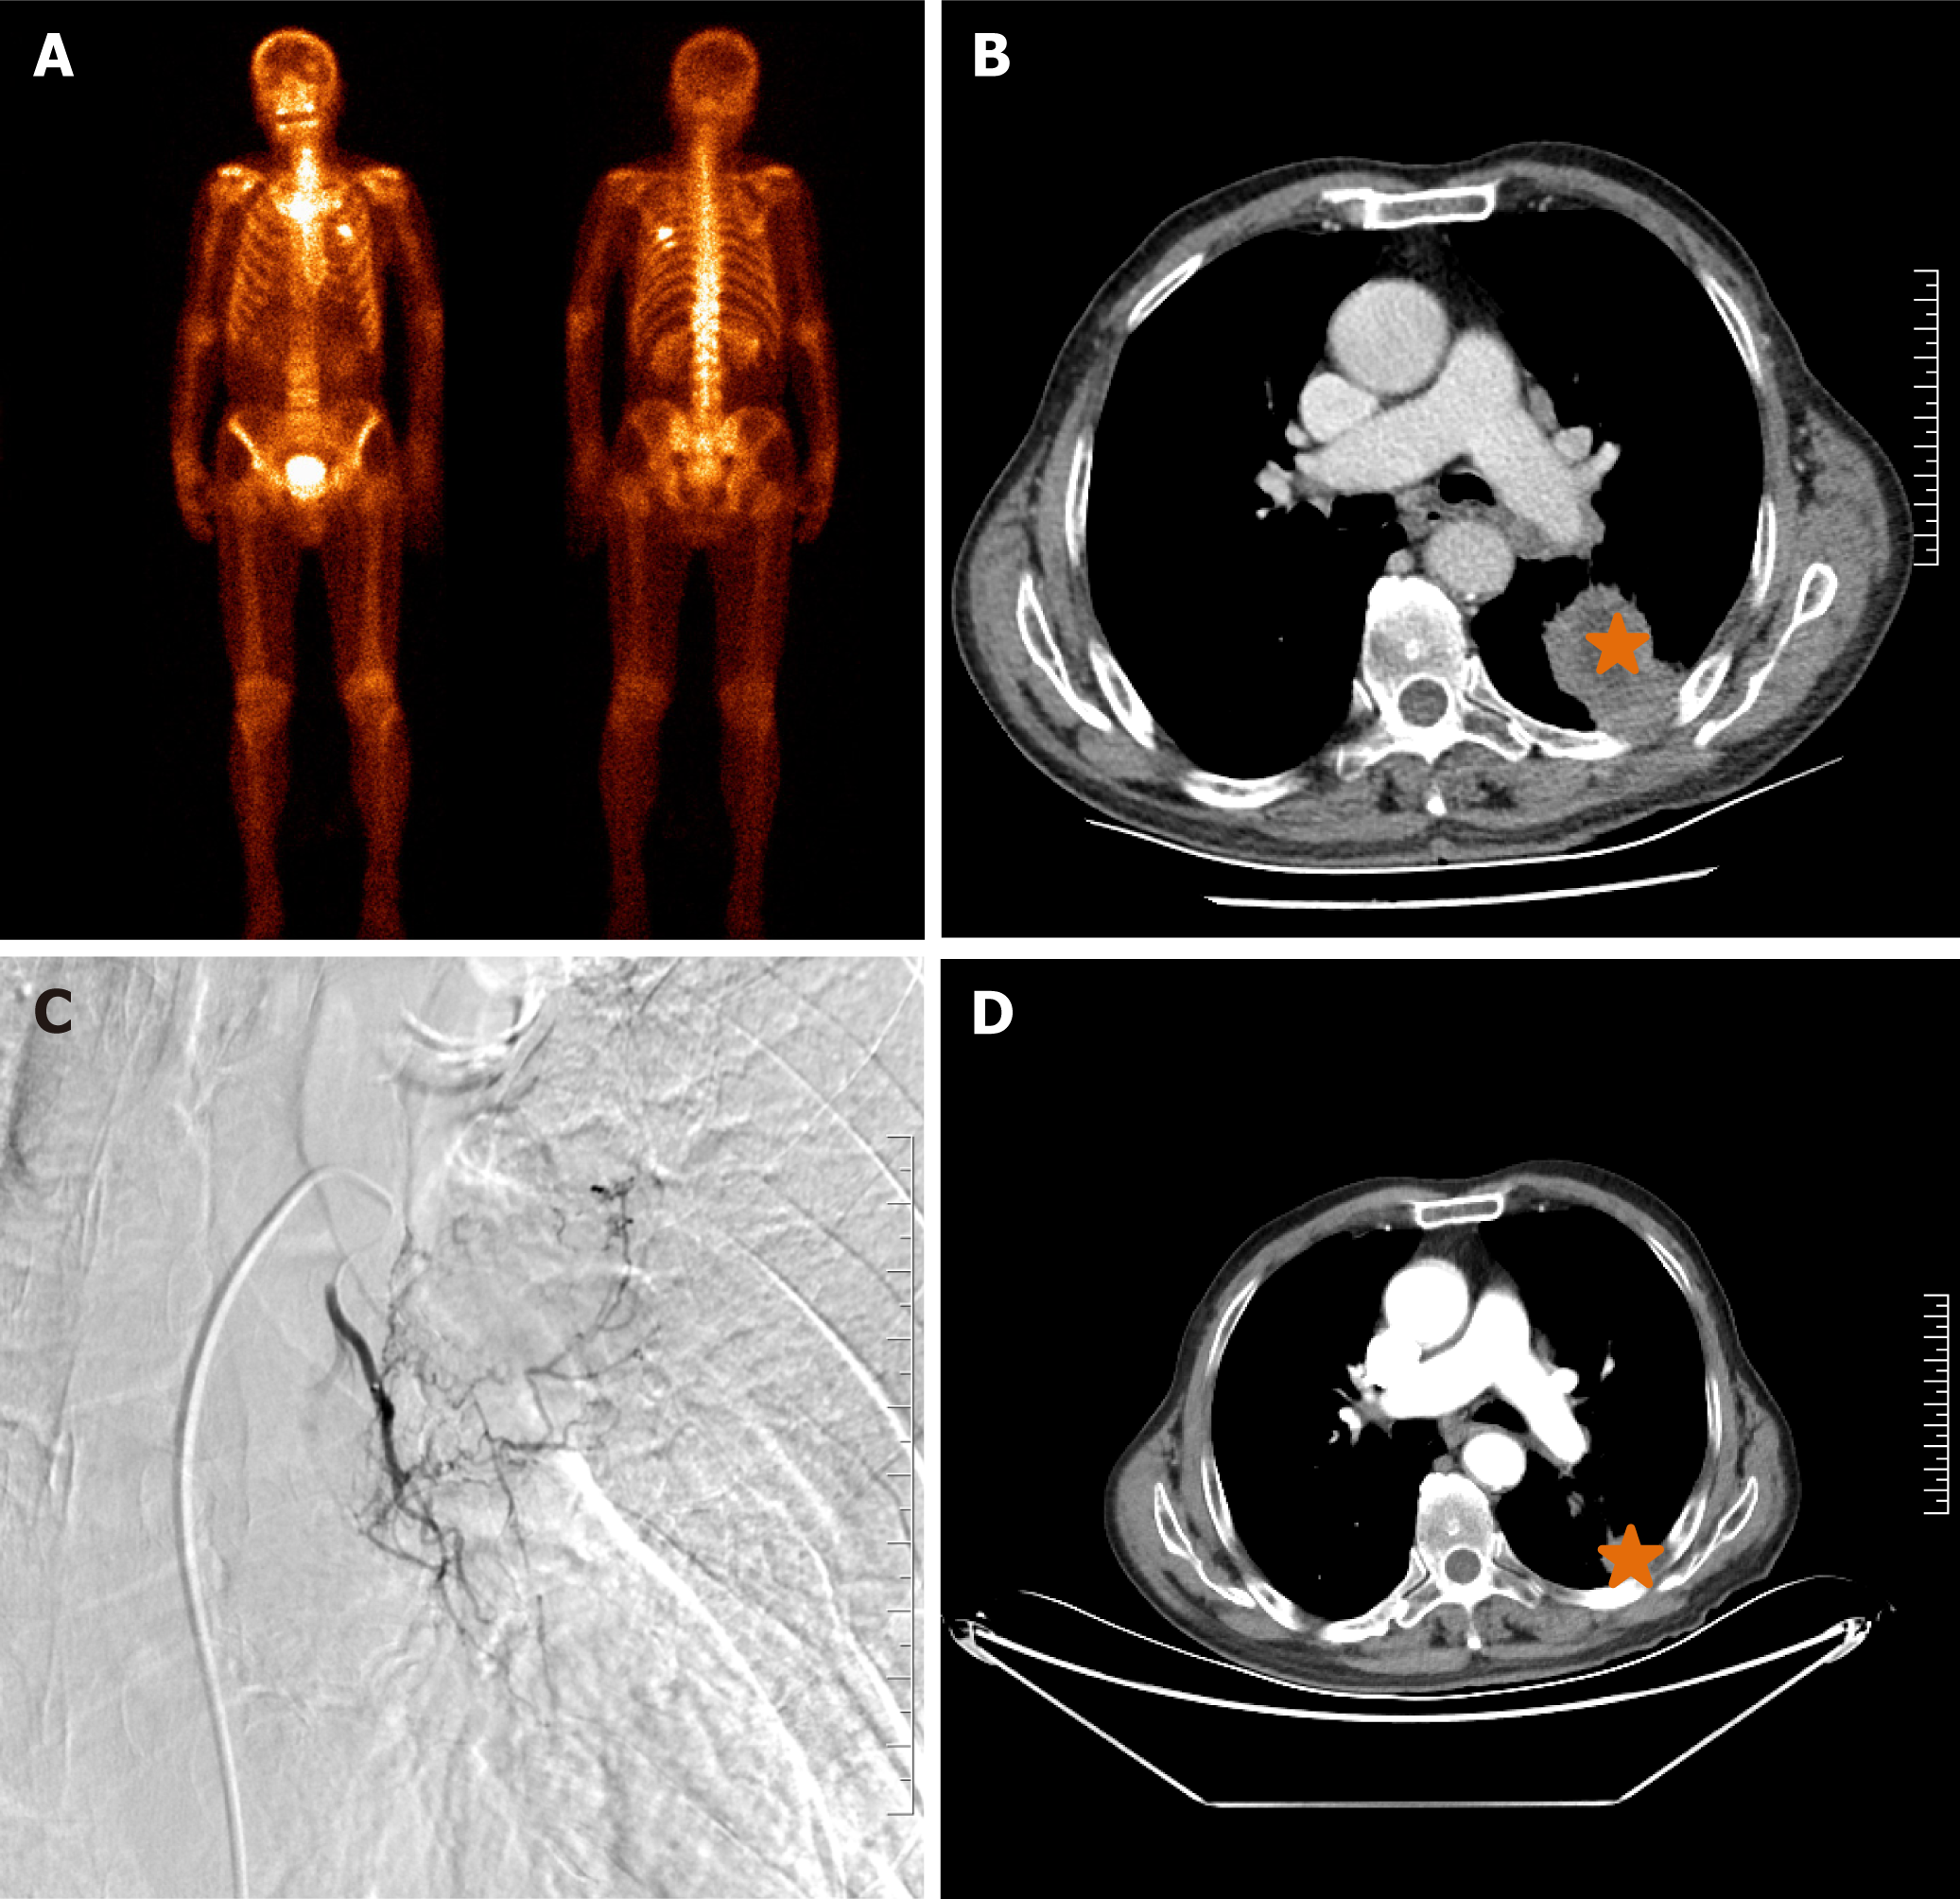

This retrospective study was approved by the Institutional Review Board of Zhengzhou university committee on human investigation, with all methods conducted in compliance with the relevant guidelines and regulations. As this study was designed as a retrospective study with clinical data analysed retrospectively and anonymously, the need for informed consent was waived by the Institutional Review Board of the First Affiliated Hospital of Zhengzhou University (No. 2023-KY-1002-002). All records were de-identified and stored in encrypted computer after data collection. A total of 123 patients with unresectable NSCLC who were treated in our department from July 2016 to July 2023 were retrospectively analysed. The inclusion criteria: (1) Biopsy proven NSCLC; (2) TNM stage II-IV according to the American Joint Committee on Cancer (AJCC) 7th Edition Cancer Staging System (Figures 1A, 2A, 2B, 3A and 3B); (3) Unresectable NSCLC or refused surgical resection due to severe comorbidities, advanced age and financial difficulties; and (4) Age 18 years to 85 years. The exclusion criteria: (1) Child-Pugh stage C or D; (2) Severe lung or heart dysfunction; (3) Severe infection; (4) Lactation or pregnancy; (5) Allergic to chemotherapeutic drugs or contrast agent; (6) Eastern Cooperative Oncology Group (ECOG) score > 2; (7) White blood cell < 3000 cells/mm3; (8) Total bilirubin > 2 mg/dL; and (9) Creatinine > 2 mg/dL.

DOX, OXA or GEM was loaded using CalliSpheres beads (Jiangsu Hengrui Medicine Co. Ltd., Jiangsu Province, China) for 30 minutes, and then mixed with iodixanol contrast developer in a 1:1 ratio before embolisation. DEB-TACE was performed under fluoroscopic guidance. After successfully puncturing the femoral artery, a 5-F sheath was inserted, and a 5-F Cobra catheter (Terumo, Japan) was inserted into the bronchial artery, intercostal artery or internal thoracic artery for angiography to identify the location of the tumour-feeding artery[14]. Next, a 2.6-F microcatheter (Asahi, Japan) was inserted into these arteries for advanced superselective catheterization. Chemotherapeutic drugs were infused into the tumour mass via the microcatheter. The total dosage of the chemotherapeutic agent was allocated according to the extent of tumour staining observed in each artery if there were three or more feeding arteries feeding the tumour[15]. Then, 1 g of drug-eluting CalliSpheres beads was used for chemoembolisation until blood flow stopped (Figures 1B, 1C, 2C, 3C and 3D).

All patients were followed up until the study endpoint or death. At approximately 1-, 3- and 6-month follow-up after treatment initiation, the treatment response was evaluated via chest CT according to the response evaluation criteria in solid tumors 1.1 criteria[16] (Figures 1D-F, 2D, 3E and 3F). Progression-free survival (PFS) was defined as the time interval from DEB-TACE treatment to disease progression or death, whichever occurred first. Overall survival (OS) was defined as the time interval from the DEB-TACE treatment to death. Objective response rate (ORR) was defined as the sum of complete response and partial response, and disease control rate (DCR) was calculated as the sum of complete response, partial response and stable disease. Adverse events were monitored and graded according to the National Cancer Institute Common Toxicity Criteria for Adverse Events version 4.03[17].